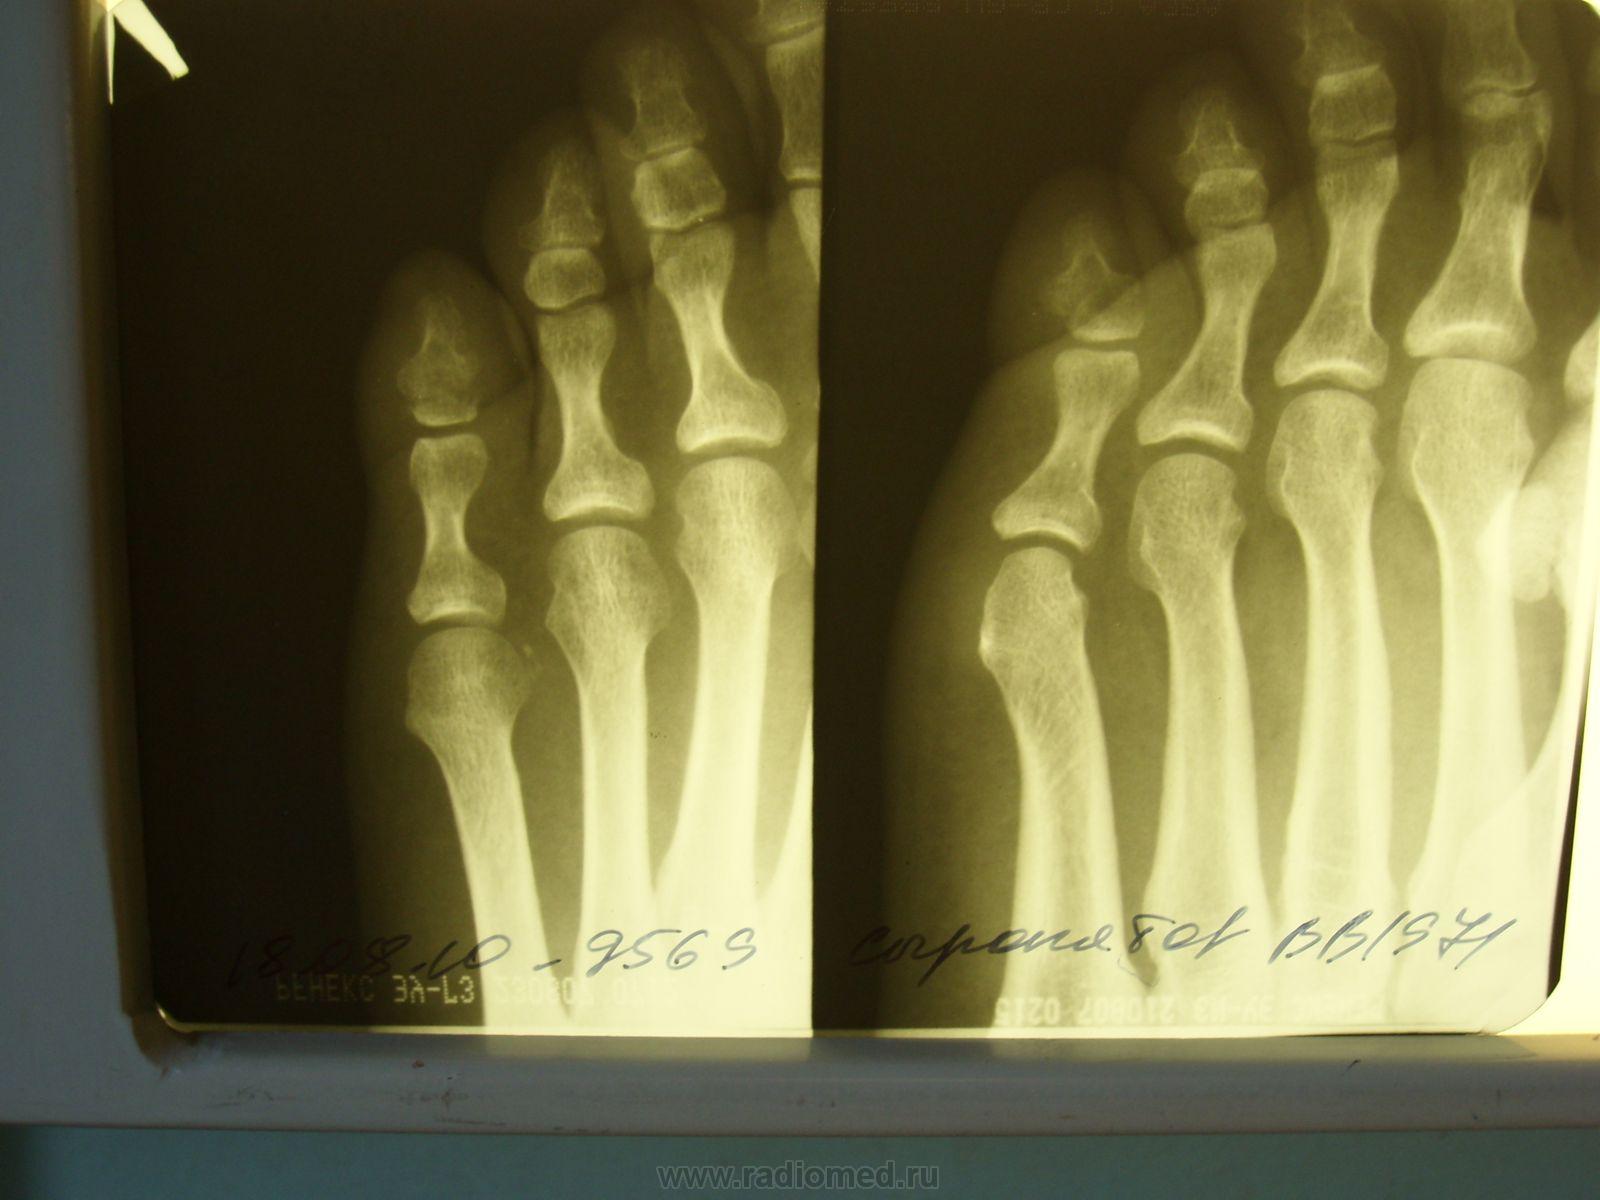

Пол пациента: Мужской пол Тип патологии: Травма Область исследования: Скелетно-мышечная система Методы исследования: Rg Молодой человек обратился в поликлиннику на болезненность и отёчность левой стопы. Был сделан снимок. https://radiomed.ru/sites/default/files/styles/case_slider_image/public/user/12/1.sl272868.jpg?itok=gmdc76MP ID:5609 Ср, 18/08/2010 - 21:59 #1 Глазков Игорь А... Не на сайте Был на сайте: 9 месяцев 1 неделя назад Зарегистрирован: 19.12.2008 - 20:41 Публикации: 1597 всвязи с подозрением на перелом ногтевой фаланги 5 пальца левой стопы. Прийди к Себе Ср, 18/08/2010 - 22:06 #2 Катенёв Валенти... Не на сайте Был на сайте: 7 лет 2 недели назад Зарегистрирован: 22.03.2008 - 22:15 Публикации: 54876 Продолжение. Приложения: Чт, 19/08/2010 - 09:56 #3 lupan Не на сайте Был на сайте: 6 лет 10 месяцев назад Зарегистрирован: 07.01.2010 - 17:17 Публикации: 1406 Данные за перелом сомнительные. Такая скиалогическая картина встречается часто, именно в V пальце стопы. Великое преймущество врача заключается в том, что он не обязан следовать собственным советам. ( А. Кристи) Чт, 19/08/2010 - 10:04 #4 Vikkur Не на сайте Был на сайте: 4 года 8 месяцев назад Зарегистрирован: 24.09.2009 - 14:34 Публикации: 1749 Если присутствует факт травмы и в связи с тем, что я не знаю о том, что такая картина частая, я бы поставил перелом.... для подстраховки выполнил бы снимок второй стопы. Виктор. Чт, 19/08/2010 - 16:05 #5 Makcimalist Не на сайте Был на сайте: 11 лет 8 месяцев назад Зарегистрирован: 08.05.2010 - 14:28 Публикации: 1994 Считаю, перелома нет! -------------- "Просто, по видимости, не видеть логики в очевидных вещах - это тоже одно из свойств некоторых умов, наряду с грустными думами о свойствах ума других." © Vega 08/10/2011

всвязи с подозрением на перелом ногтевой фаланги 5 пальца левой стопы.

Данные за перелом сомнительные. Такая скиалогическая картина встречается часто, именно в V пальце стопы.

Если присутствует факт травмы и в связи с тем, что я не знаю о том, что такая картина частая, я бы поставил перелом.... для подстраховки выполнил бы снимок второй стопы.

Считаю, перелома нет!